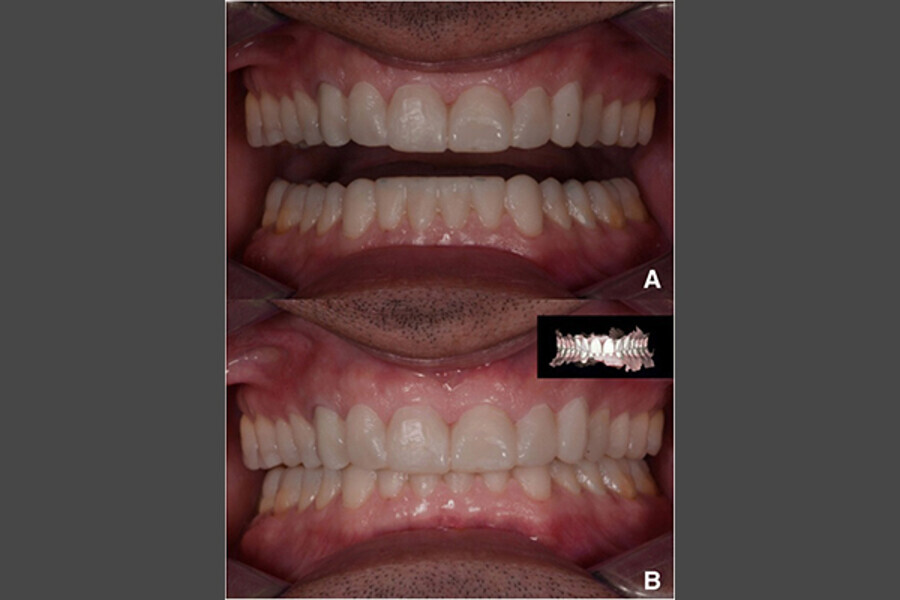

Fig. 14. Fotografías intraorales del tratamiento finalizado. a y b Vista frontal. c Vista oclusal de la mandíbula superior. d Vista oclusal de la mandíbula inferior.